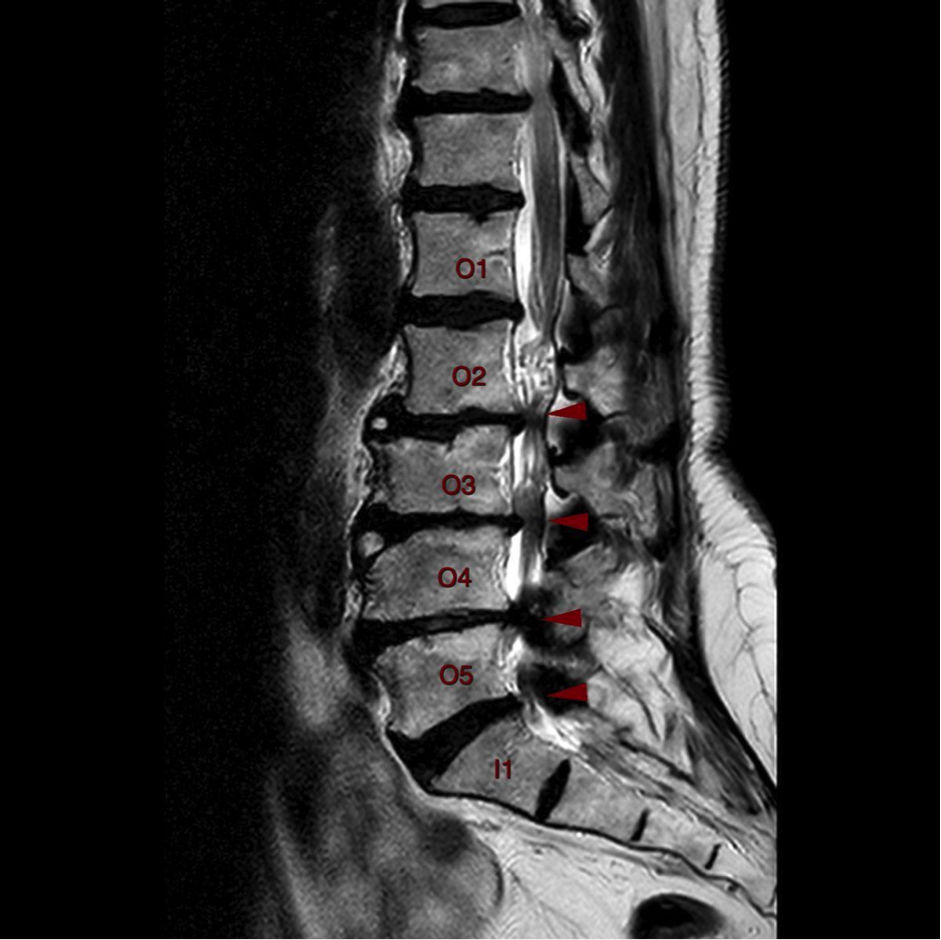

Καθοριστικό ρόλο παίζει ο απεικονιστικός έλεγχος, ο οποίος περιλαμβάνει την απλή ακτινογραφία, τη μαγνητική τομογραφία ή την αξονική τομογραφία. Η μαγνητική τομογραφία αποτελεί την εξέταση εκλογής, καθώς απεικονίζει με ακρίβεια τη συμπίεση του νωτιαίου μυελού ή των νευρικών ριζών. Σε περιπτώσεις όπου δεν είναι εφικτή η μαγνητική, μπορεί να πραγματοποιηθεί αξονική τομογραφία ή αξονική μυελογραφία. Ανάλογα με τα ευρήματα, η στένωση ταξινομείται σε κεντρική, πλάγια ή ενδοτρηματική, γεγονός που καθοδηγεί και την περαιτέρω θεραπευτική προσέγγιση.